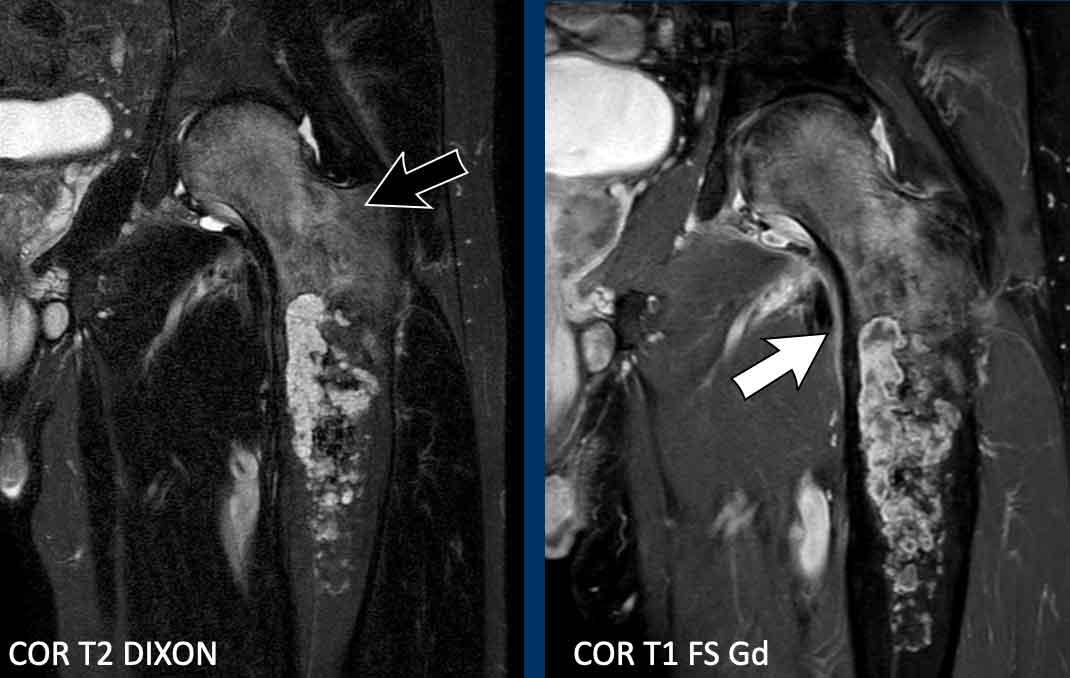

Hình ảnh

MRI xác nhận bản chất sụn của khối u với các nốt sụn tăng tín hiệu trên T2 DIXON cho thấy ngấm thuốc kiểu vách-nốt sau tiêm thuốc tương phản.

Tuy nhiên, cũng có phù tủy xương đáng kể ở phía gần (mũi tên đen) và phản ứng màng xương kèm ngấm thuốc (mũi tên trắng).

Kết luận

Các đặc điểm này rất đáng ngờ cho chẩn đoán u sụn ác tính độ cao.

Hình ảnh T1 axial xác nhận tình trạng lõm vỏ xương phía trước sâu chiếm khoảng 1/3 vỏ xương, tức là lõm vỏ xương mức độ rộng (> 10% chu vi khối u).

Cắt bỏ đầu trên xương đùi đã được thực hiện.

Chẩn đoán cuối cùng: sarcoma sụn độ II